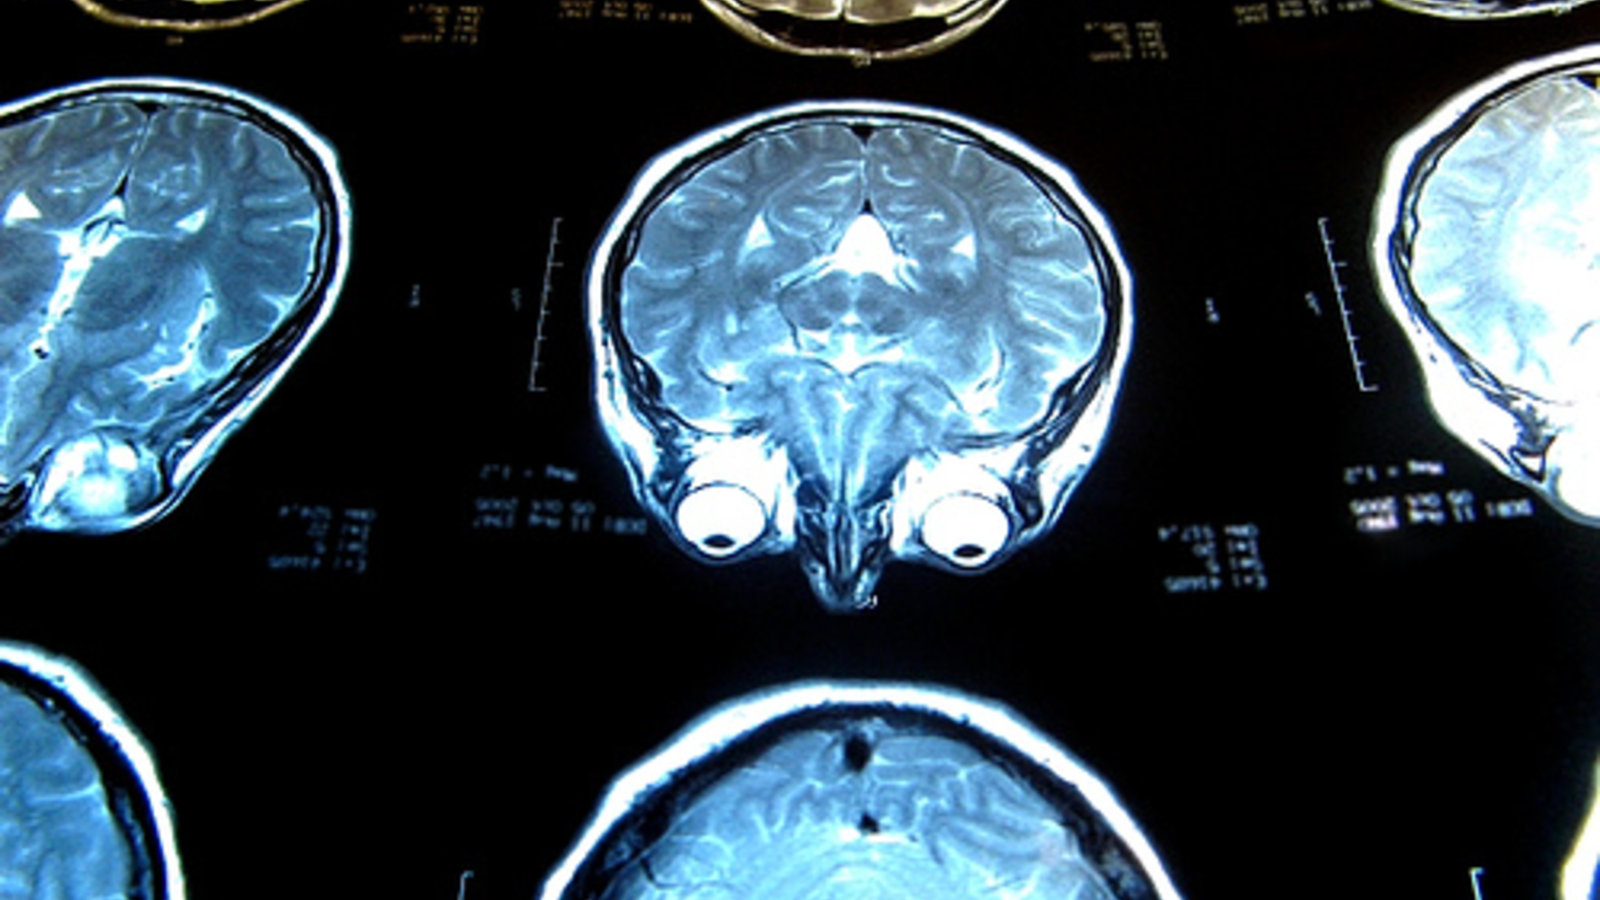

C’est à présent le tour d’une étude de chercheurs du Centre hospitalier universitaire de Sherbrooke (CHUS) de réfuter l’hypothèse controversée du chirurgien vasculaire italien Dr Paolo Zamboni, laquelle indiquait qu'une insuffisance vasculaire céphalorachidienne chronique serait à l'origine de la sclérose en plaques.